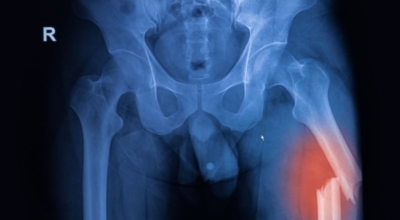

글루코사민에 대조해 원료가 100배가량 비싼 고가의 원료인것으로 알려져 있습니다. 관절염 이유가 되는 것으로는 관절 연골이 닳아 없어지기 때문인데 퇴행성 질환이라고 부르는 이유가 연골이 더 이상 생성되기 어렵기 때문이죠. 특히 콘드로이친이라는 성분이 나이가 들면서 길이가 짧아지고, 크기가 줄어들기 때문에 연골 구조가 변화되어 가면서 무릎뼈의 간격이 좁아져 통증을 유발하는 원인인데 이때 콘드로이친 효능을 바라볼 수 있어요.

콘드로이친은 대부분이 골관절염 증상 관리를 위한 치료제로 쓰이고 있습니다. 미국에서 시행된 골관절염 환자 604명을 대상으로 한 연구에서 콘드로이틴의 골관절염 통증 관리의 효과를 관찰했는데 그 결과, 콘드로이틴이 무릎 골관절염 통증이 있는 사람들의 약 10%가 통증완화와 개선효과를 체험하였습니다. 그 이유는, 노화가 진행되는 중장년층에게서 콘드로이친 수치가 저하되는걸 볼 수 있습니다.

이는 곧 연골의 뼈와 뼈 사이 완충효과 및 보호기능 약화로 이어지는데 이를 보충하면 관절염을 해결하는데 도움 됩니다. 그리고 콘드로이친은 관절세포를 재생시키는데 도움이 되고 외부 충격을 흡수, 완화하는데에도 가장 좋은 효과가 있습니다.

관절염으로 인한 통증은 환자의 몸의 기능을 쇠약하게 만들기도 합니다. 좀 더 유심히 말하자면, 관절염으로 기인해서 몸을 움직이지 않아 일상 활동과 삶의 질에 영향을 미치게 됩니다. 한 프랑스에서 모두 만들어진 연구에 의하면 12개월간 관절염 환자에게 하루에 800mg의 콘드로이친을 전달한 결과 위약을 복용시킨 대조군에 대조해 기능 역량이 50% 내외로 향상된 결과가 나왔습니다.

또 다른 연구를 보면 콘드로이친 복용이 무릎 관절의 마찰 계수를 낮추는 것으로 보여 집니다. 즉, 연골이 보다 부드럽게 움직일 수 있도록 도와 관절 기능에 도움이 되는 것 이예요.